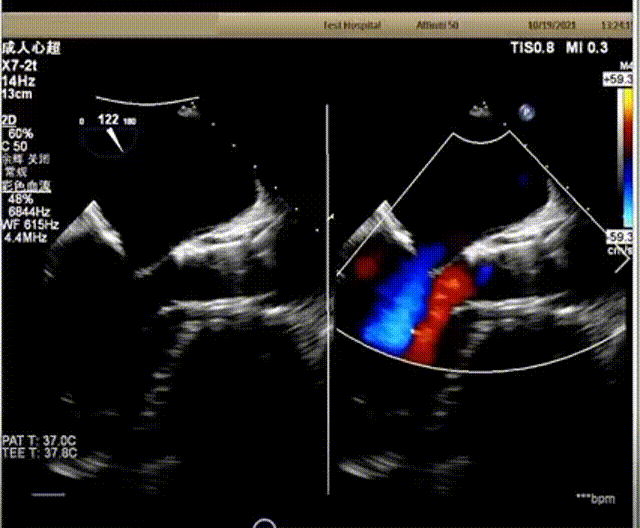

超声下血流动力学良好,微量反流